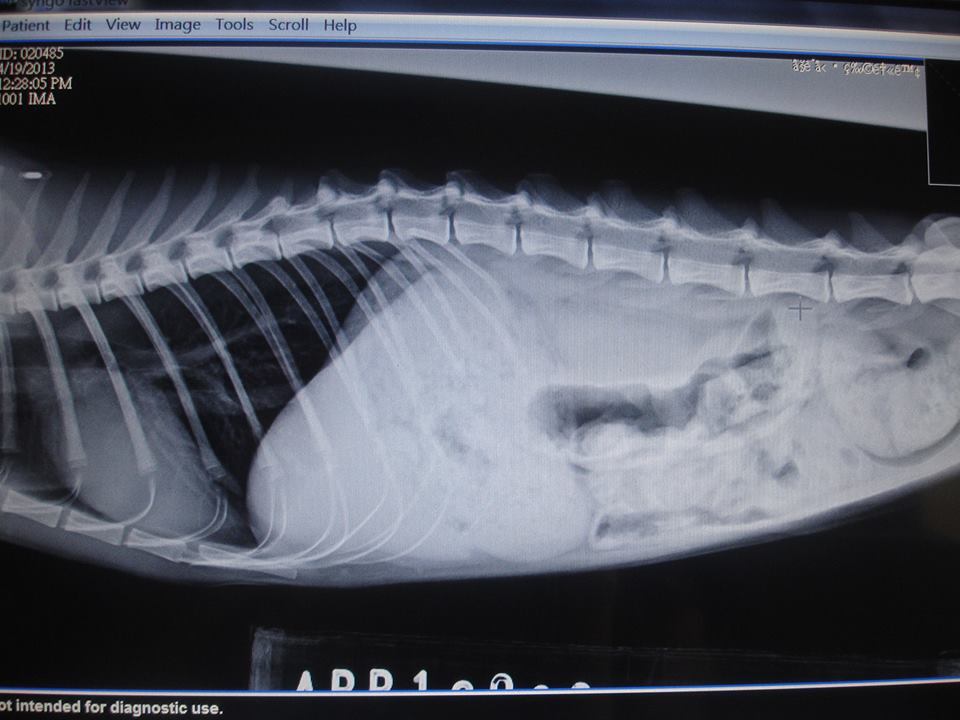

主題: 壽山收容所截肢貓∼揚揚 申請者姓名: 陳美蘭 花色: 申請日期: 2013-05-24 03:42:58 申請者部落格: 申請者臉書網址: 所在縣市/合作醫院: 高雄市/博聯動物醫院 治療費用: 18910元 需求人數: 20人 已結案 (2013-08-06 14:00:39) 報名人員: Angel Liao(已付款)、Ada Fang(已付款)、徐雅嬪(已付款)、Skynike(已付款)、Peco(已付款)、Liu Usiu Tien Tzu、Mickey Han(已付款)、Yuki Liu(已付款)、Yuki Liu、喜吱吱(已付款)、konana(已付款)、clement(已付款)、麵貓匪(已付款)、Ginny Cat(已付款)、阿貴(已付款)、Luna Tsai(已付款)、LilyC(已付款)、euca(已付款)、Joddy Li、小牛(已付款)、Sara Lee、Jau Shiang Hsieh(已付款)、Zoe Lin x2(已付款)、 候補人員: 動物病情說明: 4月19看到收容所的收容公告..揚揚血淋淋的照片.很令人震撼..他是被捕獸夾.夾斷ㄌ前腳.好可憐..所以緊急接出送治療.揚揚4隻腳都送ㄌ傷..最嚴重的必須截肢處理.另3腳的傷口縫合治療..真的可憐.揚揚好乖.乖乖的任醫生擺佈..目前出院修養.只剩3隻腳也不適合野放..所以已經安置養老∼ 動物近況說明: 經過博聯動物醫院的醫生的巧手..揚揚恢復的不錯..雖然傷口很大.慢慢也好ㄌ.拆ㄌ線..目前安置在台北中途家裡照護..感恩^^~